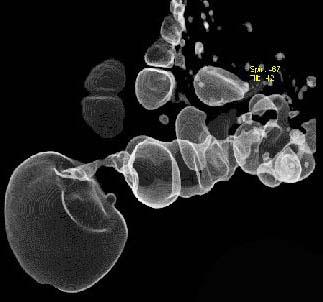

问题 女,51岁,腹胀、腹痛、进行性消瘦,影像检查如下图,最佳诊断是 ( )

选项 A.乙状结肠Crohn病 B.乙状结肠结核 C.乙状结肠癌 D.乙状结肠淋巴瘤 E.乙状结肠息肉

答案 C